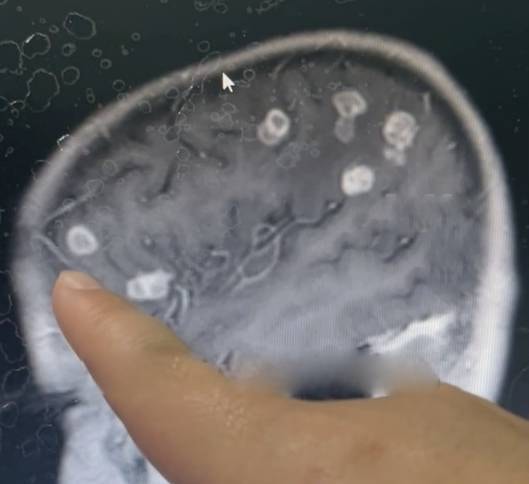

Kết quả kiểm tra khiến các bác sĩ vô cùng sốc khi não của bé bị nấm tấn công, xuất hiện hơn 20 lỗ rỗng có kích thước khác nhau, đe dọa tính mạng.

Các bác sĩ cho biết, khi bào tử nấm xâm nhập qua đường hô hấp, chúng có thể đi vào máu và tấn công mô não, gây tổn thương nghiêm trọng nếu không được điều trị kịp thời. Kết quả chụp MRI cho thấy não bé bị "gặm nhấm", tạo thành hơn 20 lỗ rỗng.